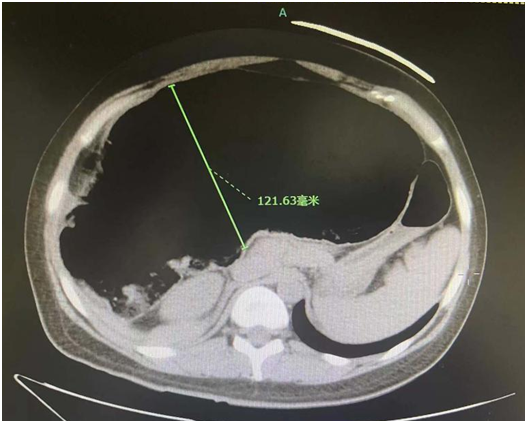

近日,29岁的王女士因腹胀难忍就诊于北京华信医院(清华大学第一附属医院)急诊科,CT结果让急诊医师倒吸了一口凉气。原来,小王的结肠已经扩张到了12cm,情况十分严重。经普外科副主任医师张子超会诊,立即收入病房。经过细致的检查和追问病史,诊断指向一种发病率仅为十万分之一左右的罕见病——假性结肠梗阻。